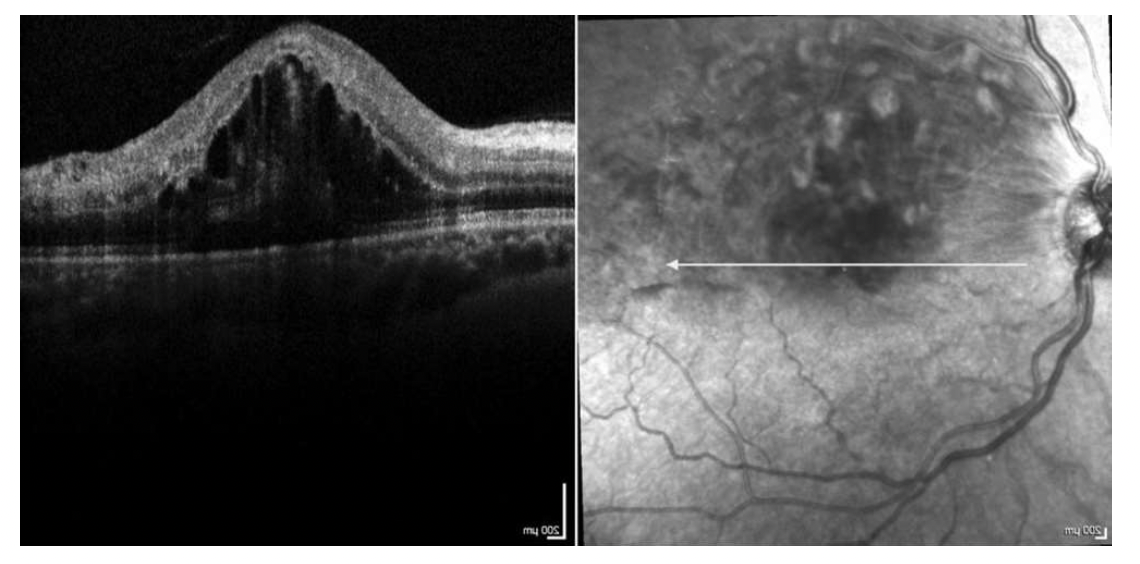

Opgave 3-1

Du er øjenlæge og ser en 74 –årig kvinde der klager over nedsat syn på højre øje gennem et par måneder.

Hun oplever at hun har sløret syn på den ene øje, hun har fået sværere ved at læse og hun har også tænkt over

at naboens flagstang ser buet ud.

Hun er kendt med diabetes, hypertension og hyperkolesterolæmi. Hun har ikke tidligere fejlet noget med

øjnene.

Du undersøger hende og finder upåfaldende forhold svarende til øjenomgivelser og bulbus.

Visus o.dxt. 0,25 (6/24). Visus o.sin 0,67 (6/9).

Ved oftalmoskopi finder du følgende:

Hvilket af nedenstående udsagn er mest korrekt?

Opgave 3-2

Basisoplysninger fra delopgave 1:

Hun ved ikke præcist hvornår symptomerne indtrådte. Hun oplever at hun har sløret syn på den ene øje, hun

har fået sværere ved at læse og hun har også tænkt over at naboens flagstang ser buet ud.

Du supplerer dine undersøgelser med en OCT-scanning: